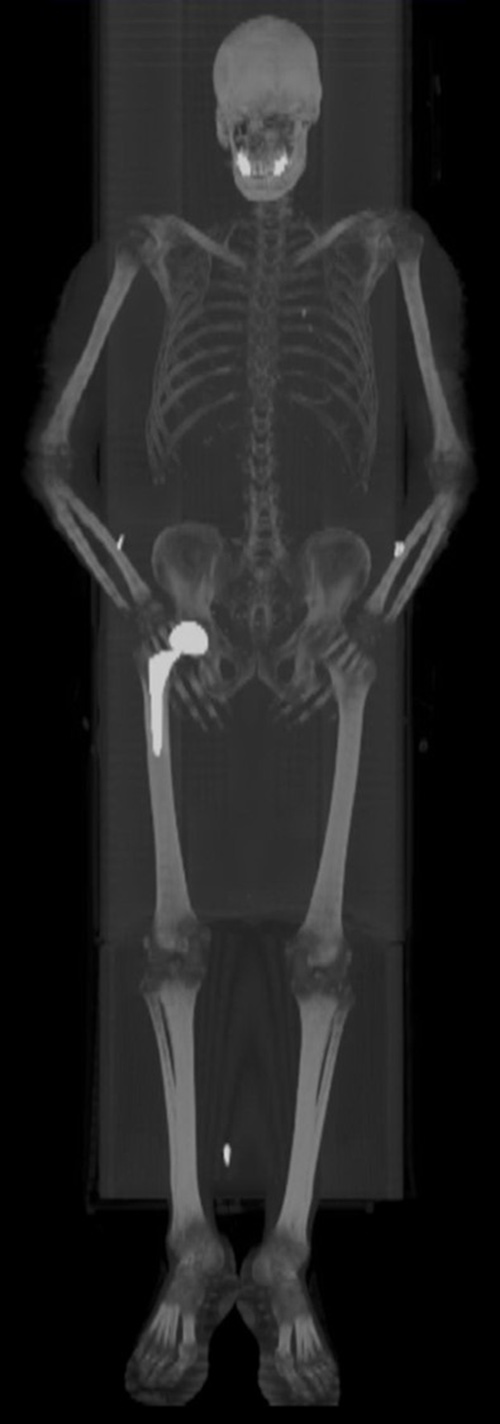

A) 50 year-old women with history of osteosarcoma of left distal femur status post resection and limb sparing prosthesis. B) Left to right, top to bottom, axial bone window CT and FDG PET, fused axial and coronal images of the lower thigh demonstrate the prosthesis within the distal left femur producing streak artifact and photopenia on the PET images. |

60 year-old women with right hip hemiarthoplasty. Axial CT bone window image (5A) demonstrates right hip prosthesis. |